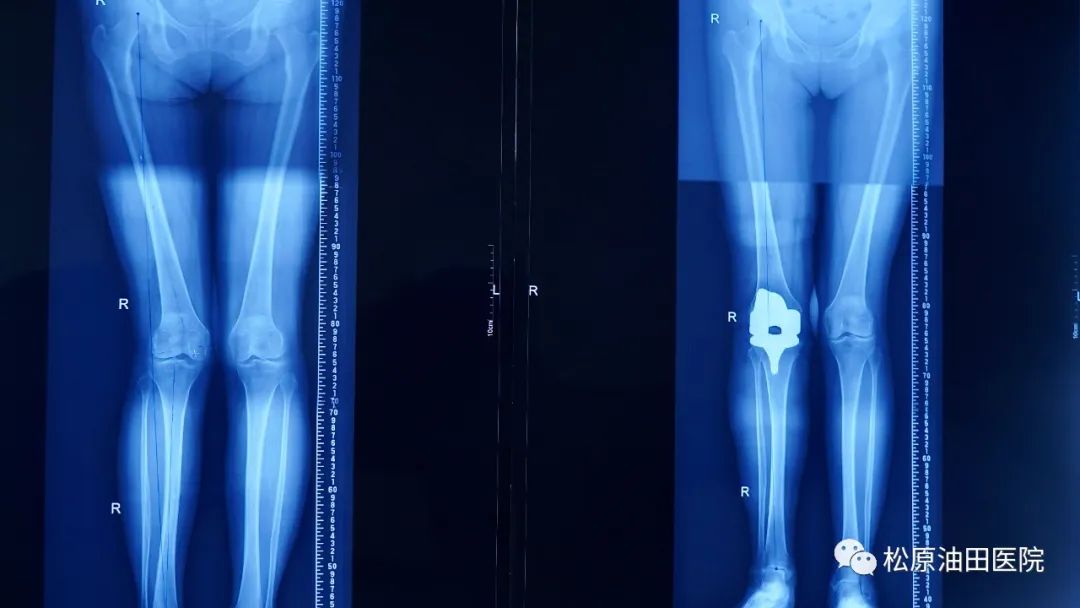

经检查,患者右膝外翻屈曲畸形,外翻角度达20度,外侧软组织挛缩,股骨外侧髁发育严重畸形,膝关节内外侧间室及前后交叉韧带均存在严重病损。

在术中过程中,发见患者膝关节股骨髁及胫骨平台关节面磨损严重,股骨外侧髁发育异常,髂胫束及外侧副韧带挛缩。针对以上病情,科室对患者外侧软组织进行了广泛松解,通过精准截骨恢复了患者下肢力线,平衡了患者膝关节屈伸间隙,手术非常成功。

术后,患者在医护人员的照顾下,恢复很快,双下肢恢复了长度,疼痛感完全消失,于术后第二天就能下床行走活动。